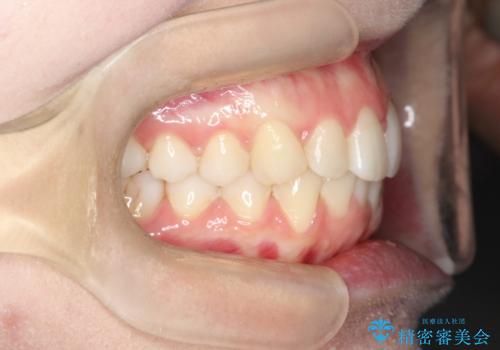

【インビザライン】前歯のガタガタをなおしたい。

- 前歯の凸凹を主訴に来院されました。

インビザラインにて奥歯の遠心移動を行いながら、前歯のガタガタを改善することができました。